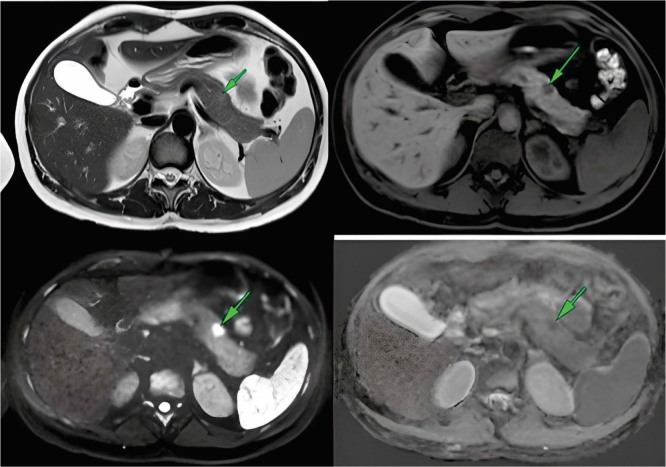

Insulinomas are rare neoplasms of the endocrine pancreas. Minimally invasive treatment options for insulinomas have gained prominence, replacing surgical resection due to its associated morbidity and mortality. Radiofrequency ablation (RFA) has emerged as a relevant treatment option. We present a case of a female patient with neuroglycopenic symptoms and severe hypoglycemic crises. The abdominal magnetic resonance imaging (MRI) showed a small nodular lesion in the pancreatic body. Laparotomy was performed, followed by RFA using a 15-mm active-tipped needle. No complications transpired, and no hypoglycemic episodes were observed during 12 months of follow-up.